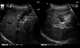

Gallbladder wall varices

Esophageal varices are extremely dilated sub-mucosal veins in the lower third of the esophagus. They are most often a consequence of portal hypertension, commonly due to cirrhosis. [Source: Wikipedia ]